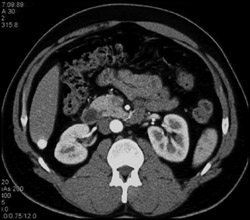

Diagnosis

Focal Nodular Hyperplasia (FNH)